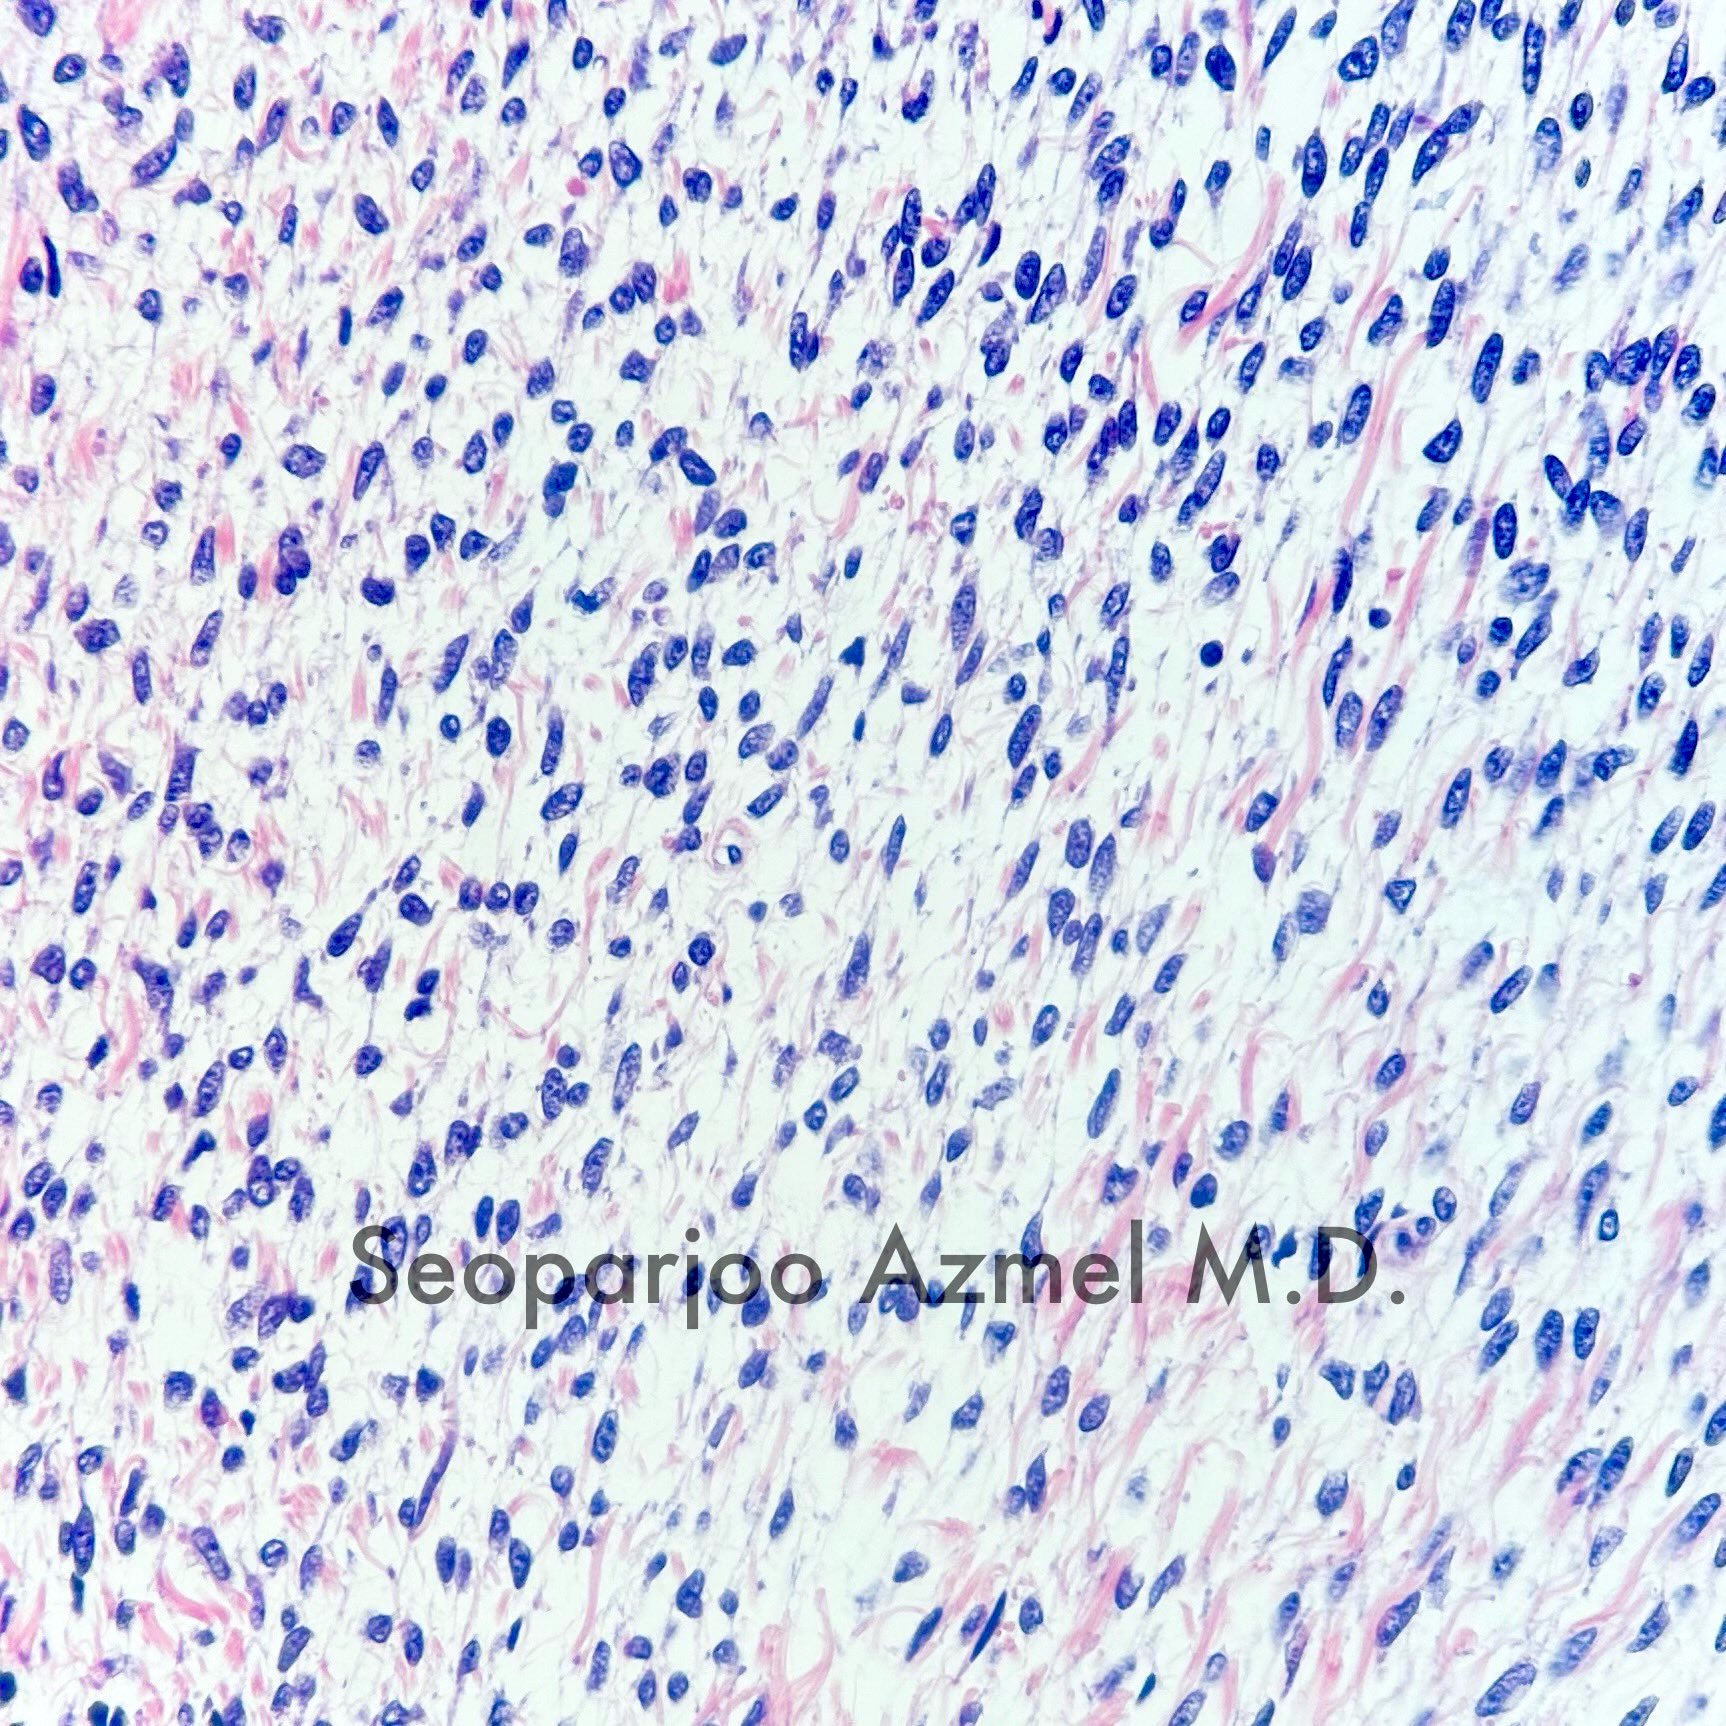

Microscopic (histologic) description

- Predominant population of cells showing ovoid to round nuclei and pale gray cytoplasm, which can be abundant

- Minor component of the tumor may have spindled nuclei, reflecting overlap between fibroma and thecoma

- Indistinct cell membranes impart a syncytial appearance

- Diffuse or nodular growth pattern

- Absent or minimal nuclear atypia

- Mitotic rate usually < 5/10 high power fields

- Hyaline plaques

- Cytoplasmic lipid vacuoles may be present but are not essential

- May show aggregates of cells with brightly eosinophilic cytoplasm (lutein cells)

- Calcification is more common in young patients (Int J Gynecol Pathol 1988;7:343)

- Uncommon features include keloid-like sclerosis, nuclear grooves, bizarre nuclear atypia (Am J Surg Pathol 2014;38:1023)

- Rarely contains a minor component of sex cord elements (Int J Gynecol Pathol 1983;2:227)

- Malignant thecoma: very rare, diagnosis requires diffuse moderate to severe nuclear atypia and high mitotic rate (> 4/10 high power fields) (Am J Surg Pathol 2011;35:e15)

Microscopic (histologic) images

Contributed by Victoria Collins, M.D., Tamara Kalir, M.D., Ph.D., AFIP and @SeoparjooAzmel on Twitter

Positive stains

- Inhibin

- Calretinin

- Reticulin stain shows a pericellular pattern (Int J Gynecol Pathol 2018;37:305)

- SF1

- FOXL2 (Mod Pathol 2013;26:860)

- WT1 (Am J Surg Pathol 2009;33:354)

- CD56 (Am J Surg Pathol 2008;32:884)

- Vimentin

- Oil red O in lipid rich cells

- GLUT5 in FDG PET positive tumors (J Obstet Gynaecol Res 2017;43:599)